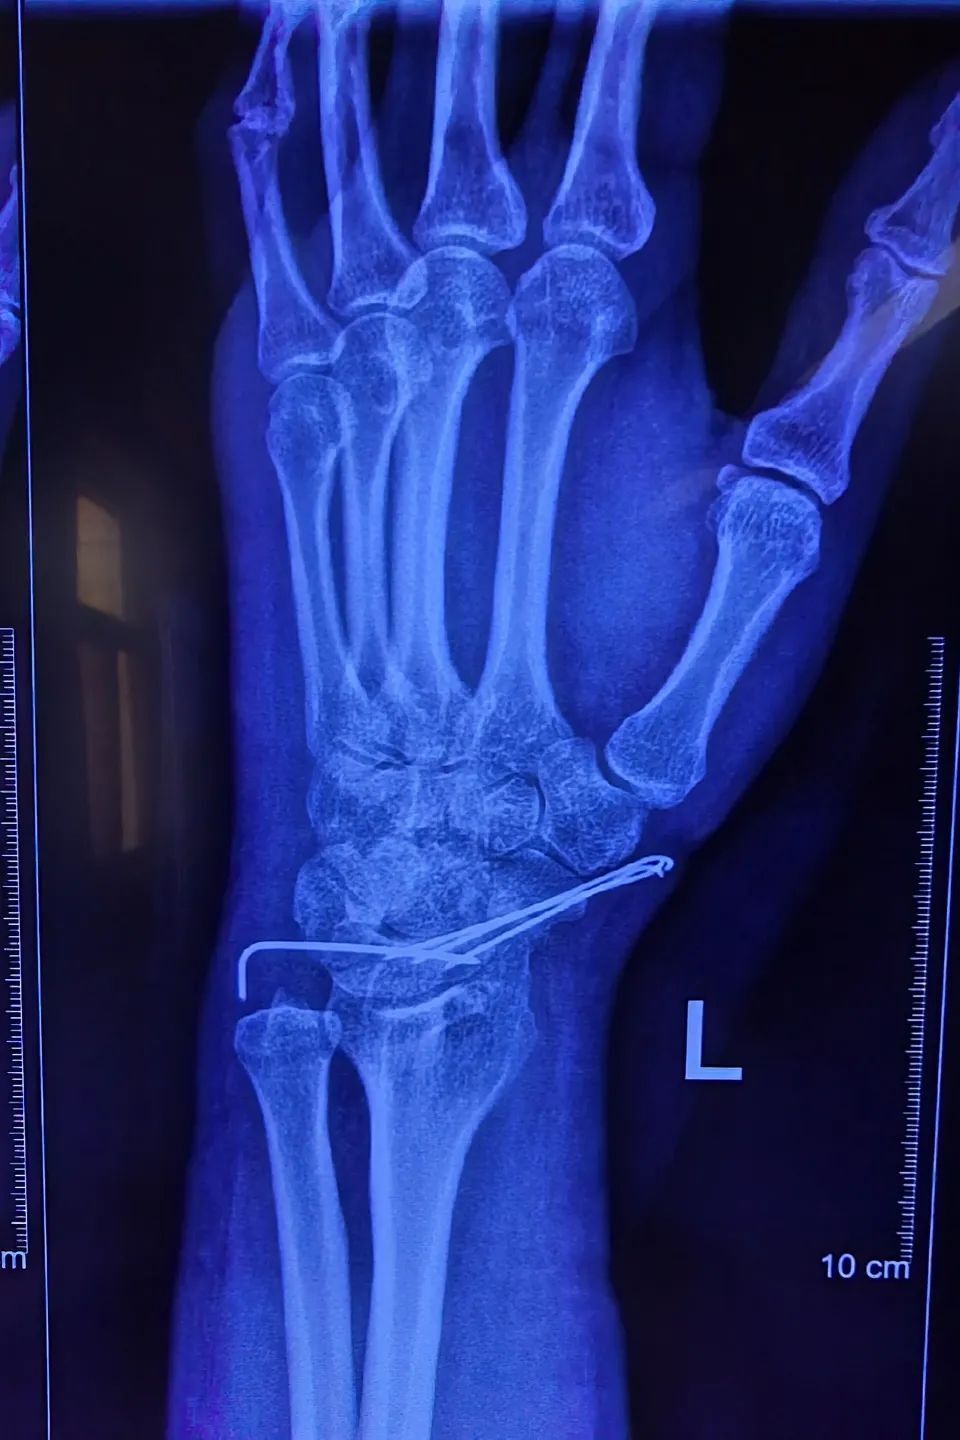

半月前,12岁的东东(化名)意外受伤,左手舟状骨骨折,武汉市第四医院

图片尺寸1200x877